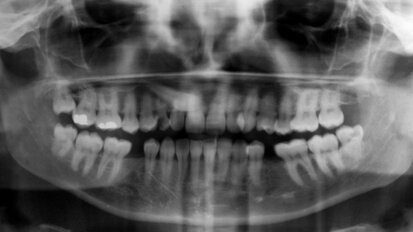

Complete reconstruction for a patient with chronic tooth decay

When oral health is neglected for extensive periods of time, dental conditions like tooth decay and periodontal disease can advance to a point that, prior ...